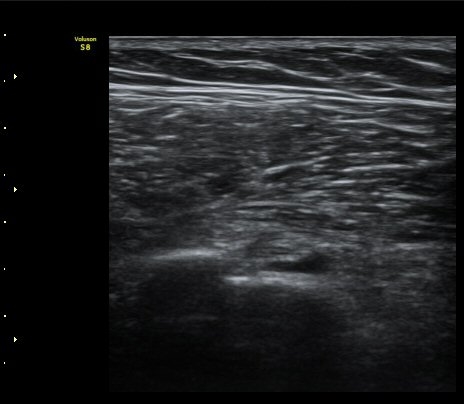

¾î±ú À̵ιڱ٠Ⱦ´Ü¸é°Ë»ç¿¡¼­ ½ÉÇÑ Á¡¾×³¶³» ¼ö¾×Àú·ù°¡ °üÂûµÇÁö¸¸ ÆÄ¿öµµÇ÷¯

°Ë»ç¿¡¼­ Ç÷·ùÁõ°¡´Â °üÂûµÇÁö ¾Ê´Â´Ù(±×¸² 1, 2).   À̵ιڱ٠¾Æ·¡ Ⱦ´Ü¸é°Ë»ç¿¡¼­

°üÀý³» ¼ö¾×Àú·ù´Â ¶Ñ·ÈÇÏÁö ¾Ê´Ù(±×¸² 3). ±Ø»ó°Ç Á¾´Ü¸é°Ë»ç¿¡¼­ Á¡¾×³¶³» ¼ö¾×